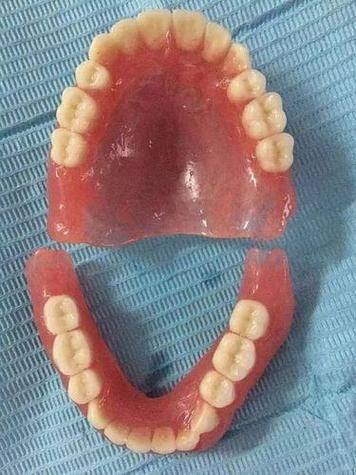

活动义齿一般多少钱一颗费用?2026年最新价格揭秘! 文章揭秘2026年活动义齿最新价格。通常镶活动假牙一颗1000 - 3000元,不同类型费用有别。如隐形义齿1000 - 1200元,便宜但寿命短、咀嚼差;钴铬合金等1500 - 2000元,强度好、使用久;纯钛基托2000 - 3000元,舒适美观。此外,地区、医院等级和医生水平也影响价格,选义齿要综合考量。 活动义齿 2026年03月04日 0 点赞 0 评论 7 浏览

活动义齿哪种最舒服还不伤害基牙?揭秘3种最佳选择! 本文围绕“活动义齿哪种最舒服还不伤害基牙”展开。首先强调了活动义齿舒适与护基牙的重要性,接着介绍了纯钛金属基托活动义齿等三种义齿的特点,包括舒适度、对基牙的影响、价格等。还给出选择建议,要考虑口腔状况、经济因素,并听取医生建议。最后提醒佩戴后注意适应期、清洁和饮食,综合考量选适合自己的义齿。 活动义齿 2026年03月04日 0 点赞 0 评论 12 浏览

补一颗活动义齿多少钱?揭秘真实费用与选择技巧! 本文围绕补一颗活动义齿的费用及选择技巧展开。费用大致在100 - 300元,受材料、修复难易、医院级别、当地经济等因素影响。不同材料义齿各有特点和价格区间。选择时要综合自身情况,选正规机构,多对比。此外,后期维护有成本,需正确佩戴清洁。提醒大家综合考量价格、质量和舒适度,必要时咨询医生。 活动义齿 2026年03月04日 0 点赞 0 评论 7 浏览